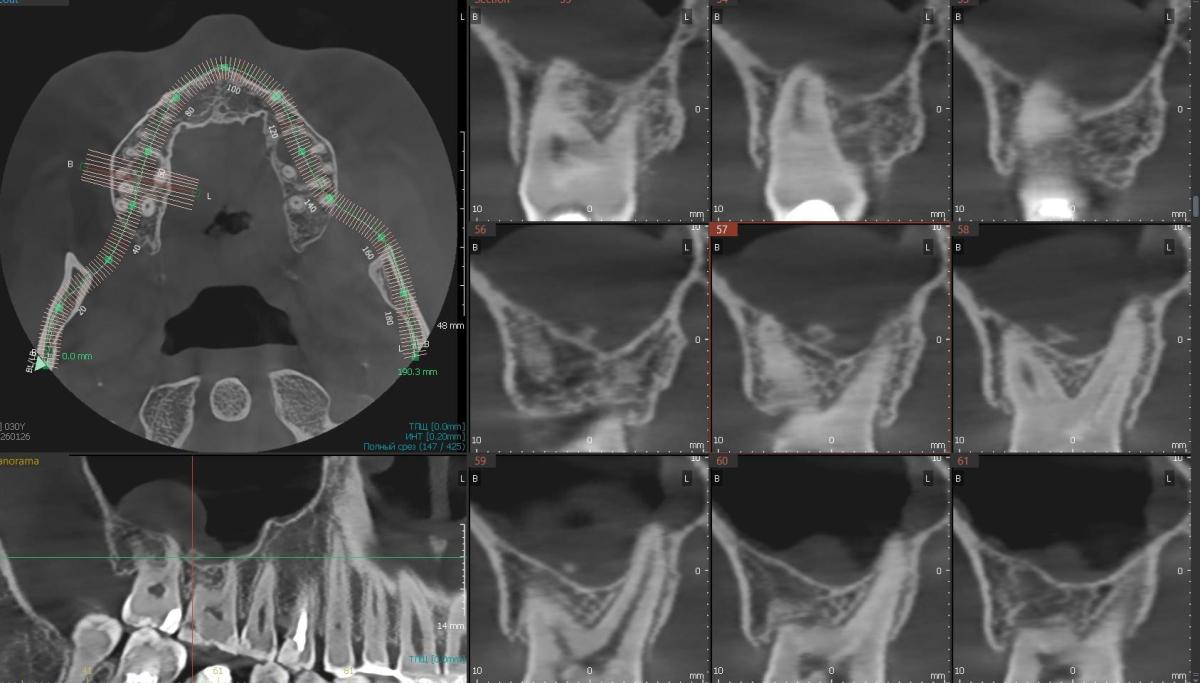

Недавно сделала кт челюстей и заметила какой-то кусочек в пазухе. Как будто кусок зуба. Может ли болеть из-за него? У меня сохранены как сувениры все удаленные зубы, я посмотрела и у одного из них как раз на корешке скол.